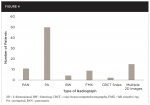

Although many patients (60) presented without any additional, unintended findings on their CBCT besides what was known and being treated, it cannot be discounted that there were still 69 incidental findings in patients who had other recent 2D imaging sent from their general dentists. The types of 2-dimensional imaging and the amount of 2D images received for patients being evaluated for the placement of future implants can be seen in Figure 4. In some instances (12), previous 2D imaging was not made available from the patient's general dentist. Even when referred with 2D imaging, some patients (17) presented with more than one incidental finding, such as a periapical radiolucency on one tooth and internal resorption on another, for example. Without the ability to visualize both arches included in the FOV when taking a CBCT, such asymptomatic incidental findings had gone unnoticed by both the practitioner and the patient.